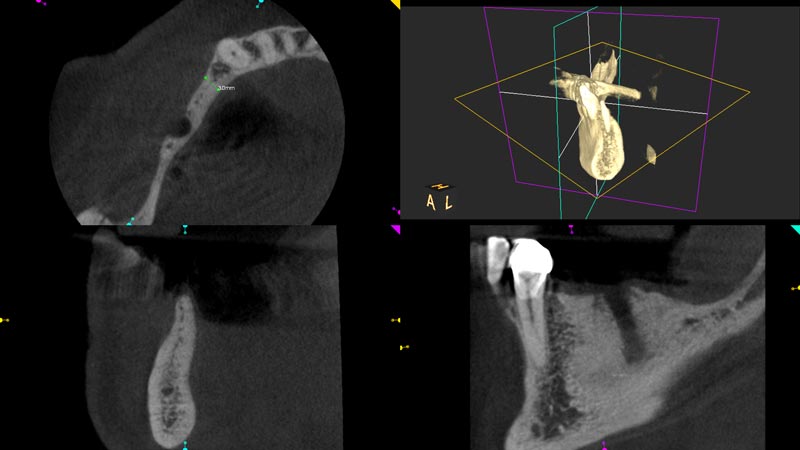

03/14 - Initial CBCT scan showing severe ridge atrophy in the right mandible

Block augmentation with maxgraft® in the mandible - PD Dr. Dr. F. Kloss